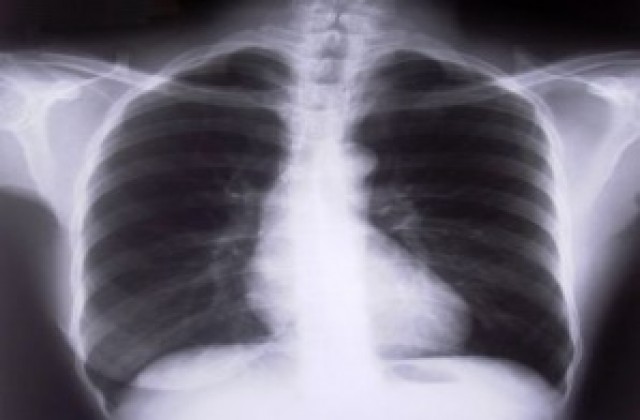

До края на октомври ще се случи фактическото пребазиране на дейността на Белодробна болница „Кудоглу" в УМБАЛ „Св. Георги". Това съобщи ресорният зам.-кмет Розалин Петков.

Първият транш от държавата е в размер на 400 хил. лева, наскоро са постъпили още 200 хиляди, а за завършване на строителството са необходими общо 800 хиляди лева. Отделно около 400 хиляди ще трябват за оборудване на помещенията, обясни Петков. Това се налага заради новите разпоредби, свързани с престоя и лечението на туберкулозно болните. Всеки пациент ще бъде настанен в единична стая с климатик и съответните удобства.

Дейността по лечението на туберкулозата е национална политика и е редно тя да се извършва в държавна болница, каквато е УМБАЛ „Св. Георги", допълни Петков.